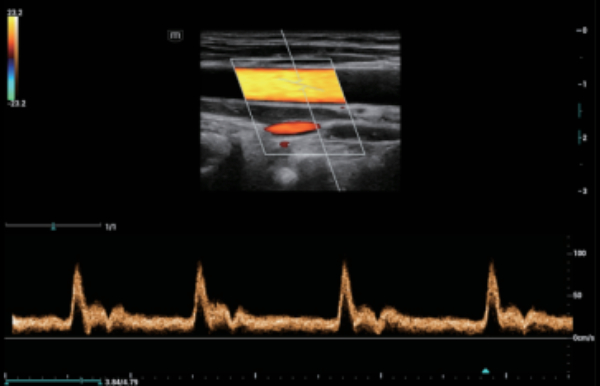

Indipendentemente dalle attività svolte in ospedale o in clinica, oppure se si desidera affinare le proprie capacità nella diagnostica per immagini generale negli ambiti della salute della donna o cardiovascolare, questa serie di soluzioni fornirà potenti strumenti per essere sempre un passo avanti.

Soluzioni di diagnostica per immagini complete con tecnologia ZST+

La piattaforma ZST+ è un'innovazione straordinaria, che rappresenta un'evoluzione nel campo dell'ecografia. Grazie alla trasformazione delle metriche a ultrasuoni dal beamforming convenzionale all'elaborazione basata sui dati di canale, supera la tradizionale limitazione del trade-off tra risoluzione spaziale, risoluzione temporale e uniformità dei tessuti, offrendo una qualità d'immagine eccezionale per infinite soluzioni di imaging con miglioramenti continui.